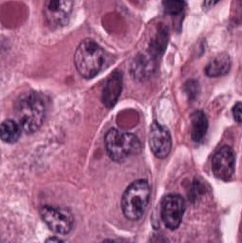

However, nuclei and glands instance segmentation cannot be regarded as a simple task for non experts in pathology labs. Despite being continuous advancements in learning algorithm, nuclei segmentation is still an extremely challenging task because of blurred nuclei boundaries, differences in size and shape highlighted by Vahadane et al. [12], uneven staining, pathological changes on pathological images, morphological abnormalities [13] and substantial color variations described by Rashmi et al. [14]. Similarly, varying morphology of glands at different histological grades, different intrinsic features of glands WSIs poses major challenge during segmentation of instances. Firstly, applying mathematical shape model for instance segmentation gets difficult due to shapes heterogeneity. Figure 2 shows structural variations of nuclei in different organs. Secondly granule filled cytoplasm cause nucleus extrusion to flat shapes as compared to oval or round structures in normal cases mentioned by Yan et al. [15]. Thirdly, cellular matrix variations results in anisochromasia thus resulting in additive noise in background compared to normal intensity gradients.

Improper staining often times result in similarity in nuclei to cytoplasm or background colors thus yielding blurred boundaries [16]. Moreover occurrence of several overlapping nuclei in whole slide images causes further difficulty in objects segmentation. Major challenge in model development is varying types of nuclei e.g nerve cell nuclei are typically triangular in shape [17], while glial and oligodendrocytes nucleus are usually round in appearance but the later one have light rings as, astrocytes have oval shape, endothelial cells are usually slender in structure [18], while malignant tumor cells have irregularly shaped nuclei [19]. Developed model is supposed to be robust enough to detect all these kinds of nuclei without any mislabelling. Digital image quality variation, background clutter, image artifacts are some other extremely important yet least discussed problem in this domain. Nuclei curvature variation also impacts detection since normally in pathology images, nuclei contour points curvature changes smoothly [20]. However, given a single contour having two or more touching or occluding nuclei, results large curvature change at touching points. Already existing automated medical image analysis tool use classical segmentation including active contour models, watershed or thresholding techniques for nuclei instances identification. These tools needs configuration with respect to each data to accurately analyze distinct microscopic modalities including scales and experimental variation, thus leading to an evident requirement of technological domain expertise for accurate algorithm selection and parameters adjustment. Still for proficient ones too, this choice can be daunting, considering that every year numerous papers are published, presenting new research techniques for gland and nucleus instance segmentation. Even after examining under controlled experimental conditions, no single technique can be generalized for segmenting all microscopy images correctly, since classical machine learning algorithms are either sensitive to technical artefacts or often fails in adapting to biological samples heterogeneity. Altogether, this situation yields slows pace of research and at times inhibits research laboratories from adopting newer image analysis technologies owing to the time and expertise required.